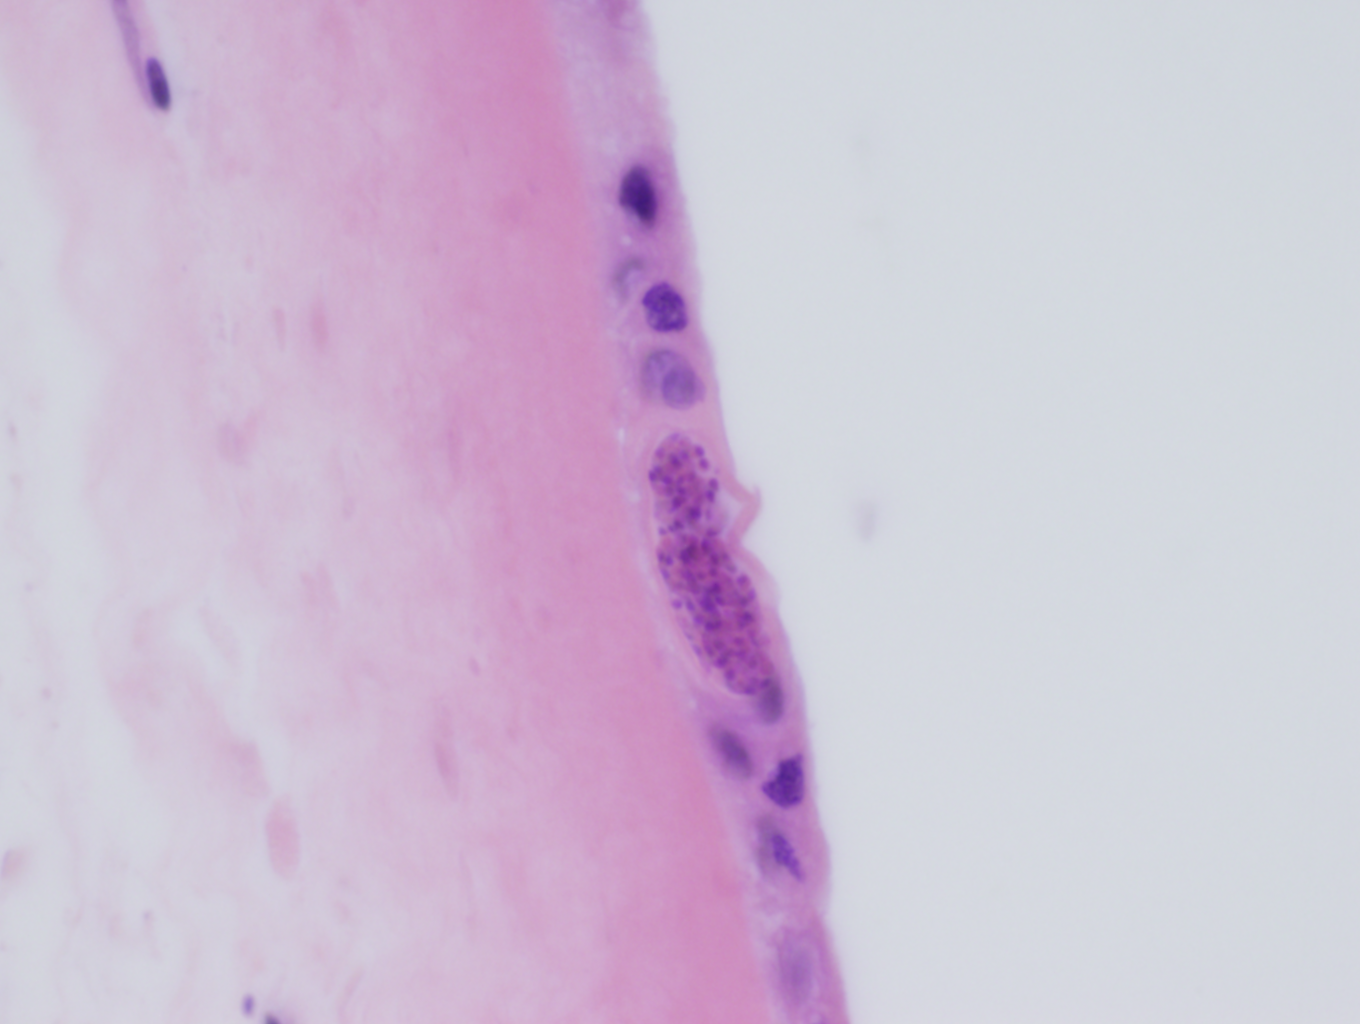

Routine microscopic sections demonstrated round to elongate cysts within the amnion of the fetal membranes (Figures 1a & 1b) and within the Wharton’s jelly of the umbilical cord (Figure 2). These cysts measured approximately 50 microns in diameter and had a thin, translucent cyst wall. Within the cysts were innumerable small round “dot-like” forms which could best be appreciated by focusing up and down through the plane of the section.

The histologic features are diagnostic of congenital Toxoplasmosis. The case was sent to the reference laboratory, where immunohistochemical staining for Toxoplasmosis demonstrated positive staining within the tissue cysts.

The life cycle within the intermediate host involves two morphologically distinct stages, the tachyzoite and the bradyzoite. When infective oocysts are ingested by an intermediate host, they transform into tachyzoites, which are able to invade the intestinal epithelium and then widely distribute throughout the body. Tachyzoites are crescent-shaped, non-encysted and measure from 3-7 microns in length by 2-4 microns in diameter. They migrate preferentially to the muscle and neural tissues, where they eventually develop into tissue cysts, which are known as bradyzoites. Bradyzoites are much larger than tachyzoites (approximately 50 microns), are round to elongate and contain numerous “dot-like” parasitic forms encased within a thin cyst wall. Tachyzoites are eventually cleared following acute infection, but the intermediate host remains chronically infected with bradyzoites. If the host becomes immunocompromised, the bradyzoites differentiate into tachyzoites, which then recirculate through the body leading to reactivation of latent disease.